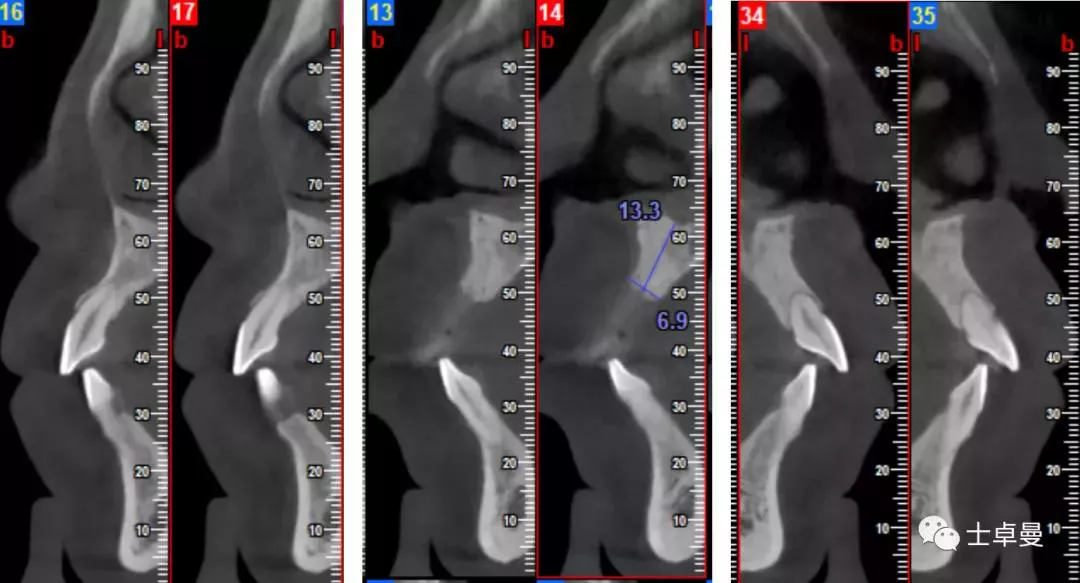

影像学检查

·      CBCT显示11可用骨高度13.3mm,宽度6.9mm;

·      12近中牙槽嵴吸收至根尖1/3处,远中牙槽嵴吸收至根1/2处;

·      21可见根吸收影相,近中牙槽嵴吸收至根尖1/3处;

·      22牙槽嵴近中吸收至根1/3处,远中吸收至根尖。